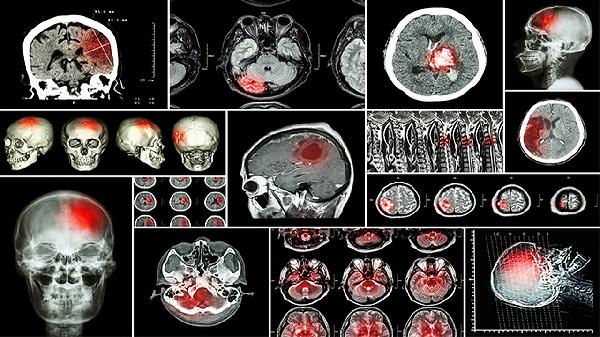

颅内感染会呕吐吗 颅内感染的常见症状细说

颅内感染可能会出现呕吐症状。颅内感染的常见症状主要有头痛、发热、呕吐、意识障碍、颈项强直等。